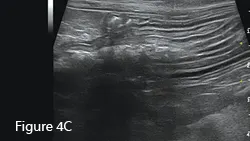

Ultrasound image of an enlarged intestine (arrows) showing large amount of reverberation artifact (arrowheads) caused by luminal gas. This prohibits visualization of the far wall of this loop of bowel. The ultrasound impression was a distended colon.